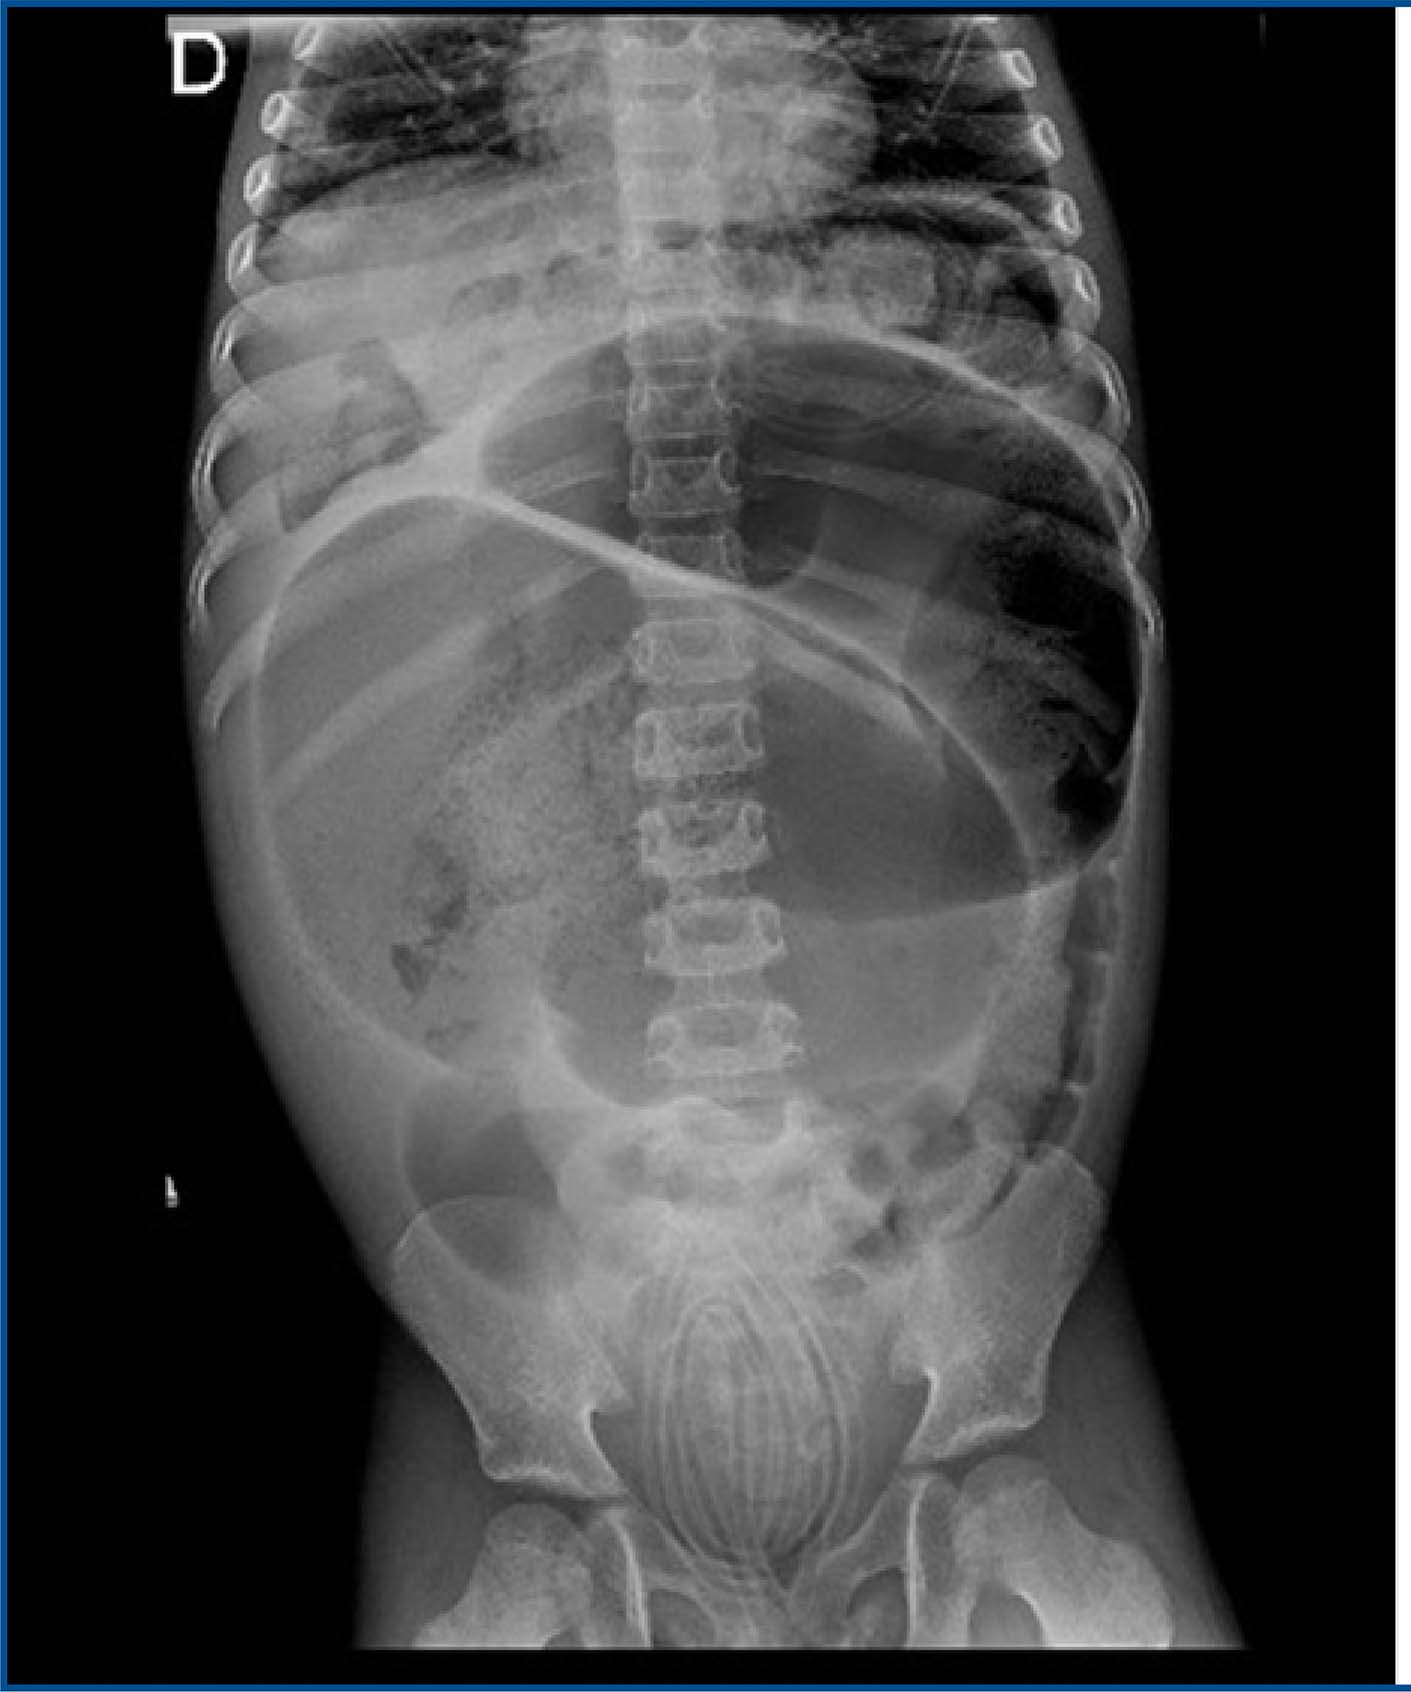

During the most recent outpatient visit, a significant fecal impaction was again identified, requiring surgical removal. Following the procedure, the patient remained hemodynamically stable, but experienced prostration, abdominal pain, poor oral intake tolerance, and diffuse abdominal tenderness on palpation, without signs of peritonitis. An abdominal X-ray was performed (figure 1), and the patient was started on a regimen of antibiotics, cessation of oral intake, basal maintenance fluids, and optimized analgesia.

Figure 1 : Abdominal X-ray with no evident abnormalities

Although hemodynamically stable, the patient continued to report intermittent abdominal pain. On physical examination, the abdomen was tense, with no rebound tenderness. Given these findings, a follow-up upright abdominal X-ray was ordered (figures 2 and 3), as the initial supine bedside X-ray showed no significant abnormalities.